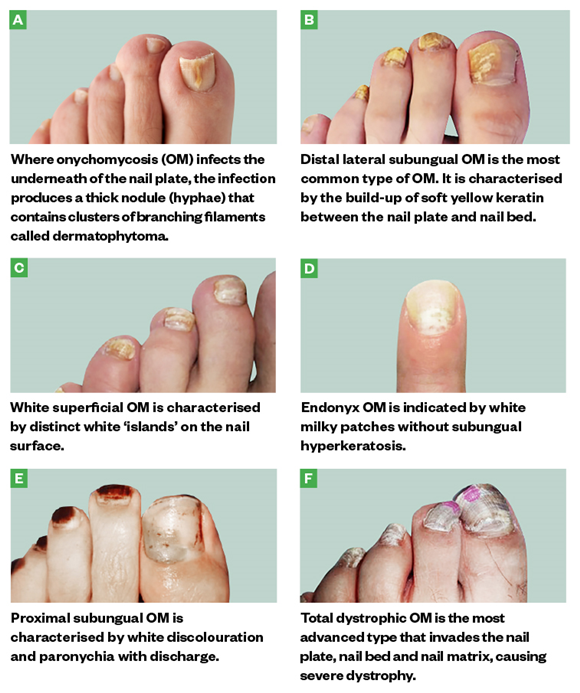

Onychomycosis progressively changes the toenail’s quality and colour …

eTalk : Onychodystrophy vs Onychomycosis

Onychomycosis progressively changes the toenail’s quality and colour …